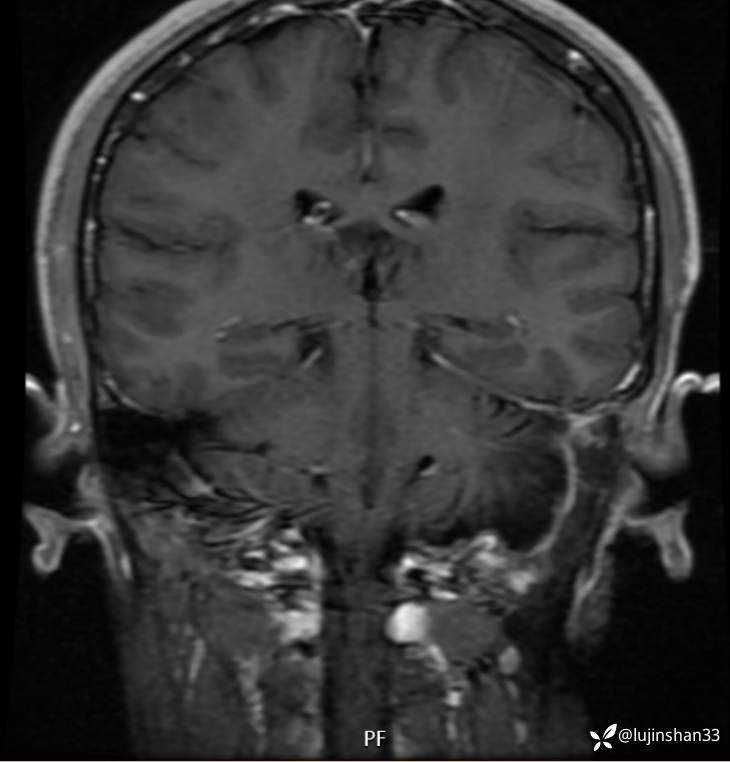

二次手术后1年半,肿瘤切除术后,未见复发

【治疗经过及结果】:左侧颞枕入路颞骨枕下骨巨细胞瘤切除,腹部脂肪填充